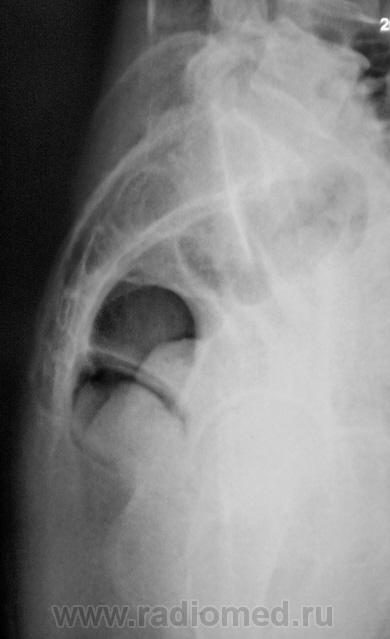

Боковая.

Посттравматический симфизит - это такой медицинский диагноз есть? Тогда уж лучше - симфизопатияУлыбаюсь.  По поперечному перелому Л5 - тангенциальный эффект, сложение теней. По хорошему, надо бы доснять поясничный отдел позвоночника, в том числе в косых проекциях - на дугоотростчатые суставы, и грудо-поясничный переход.

2. А на боковой массе крестца справа разве не линия консолидирующегося перелома?

Верятность перелома остистого отростка Л4 очень велика. Это находит подтвеждение и на боковом снимке.